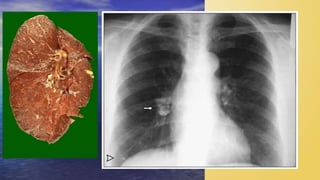

 Chest CT scan

• Any abnormality in chest radiography

-SPUTUM SMEAR

-CHEST X RAY